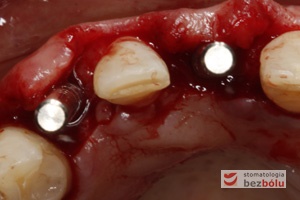

Implanty in situ - widok okluzyjny wprowadzonych wszczepów 1 mm podwyrostkowo

Implanty in situ – widok okluzyjny wprowadzonych wszczepów 1 mm podwyrostkowo

Miniśruby chirurgiczne wprowadzone do implantów - miniśruby zapewniają łatwiejszą identyfikację miejsca wszczepu przy ekspozycji

Miniśruby chirurgiczne wprowadzone do implantów – miniśruby zapewniają łatwiejszą identyfikację miejsca wszczepu przy ekspozycji